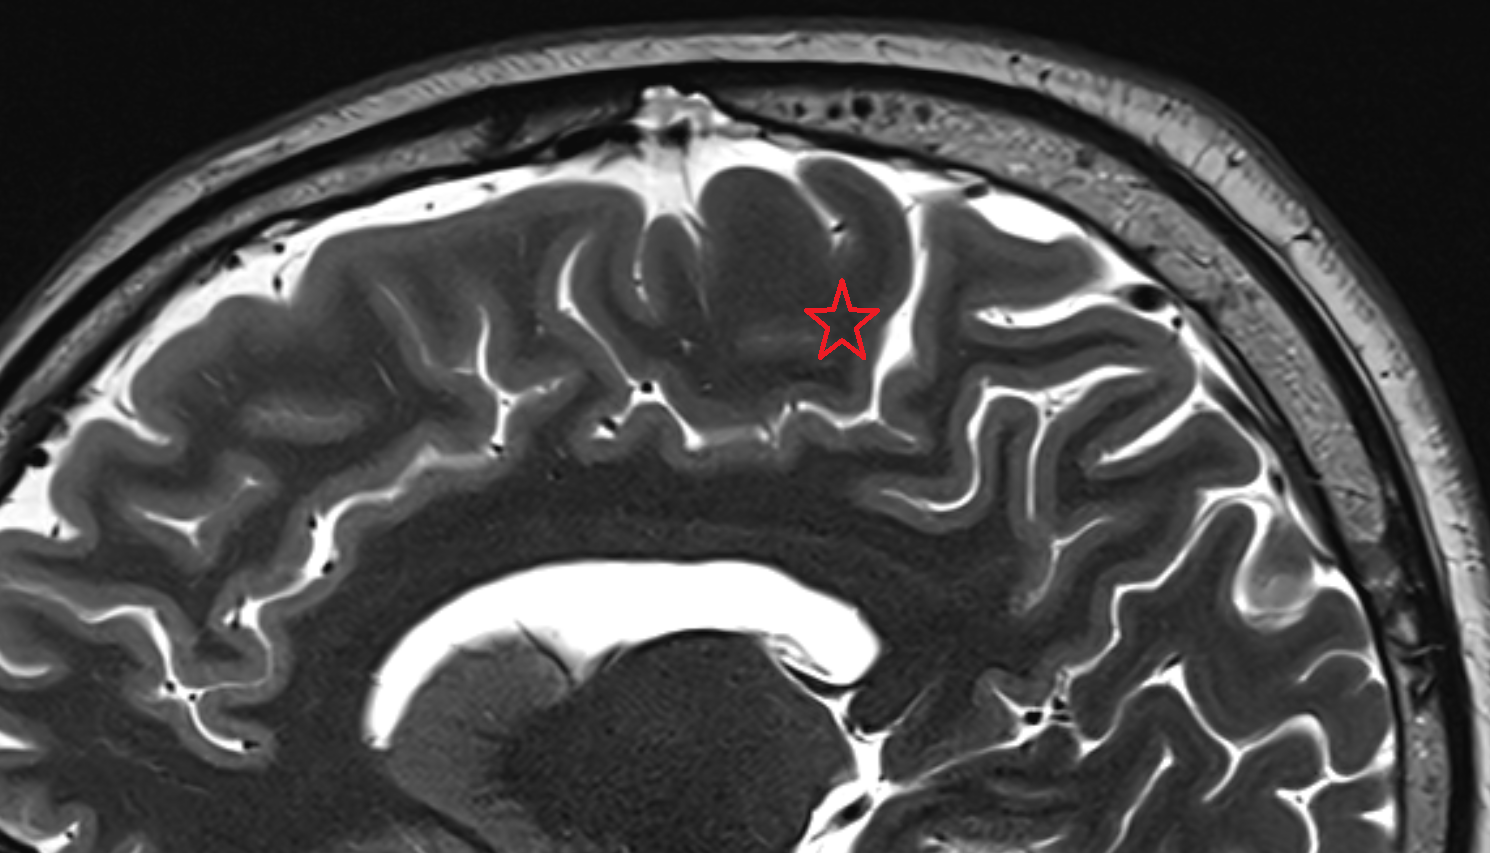

- Central sulcus